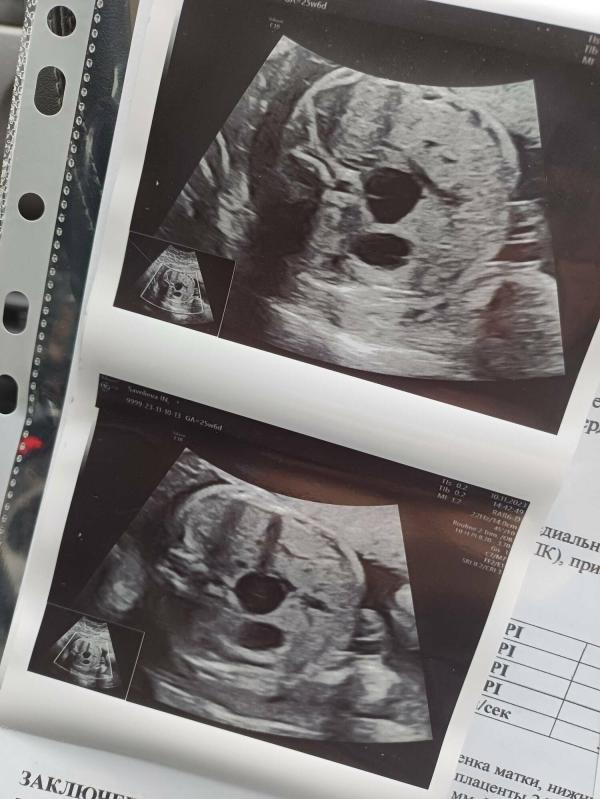

Моя крошка🥰

Когда смотрю на такие фото думаю:

Бедные дети, еще не родились, а мамы уже на них контент делают и спокойно расти не дают